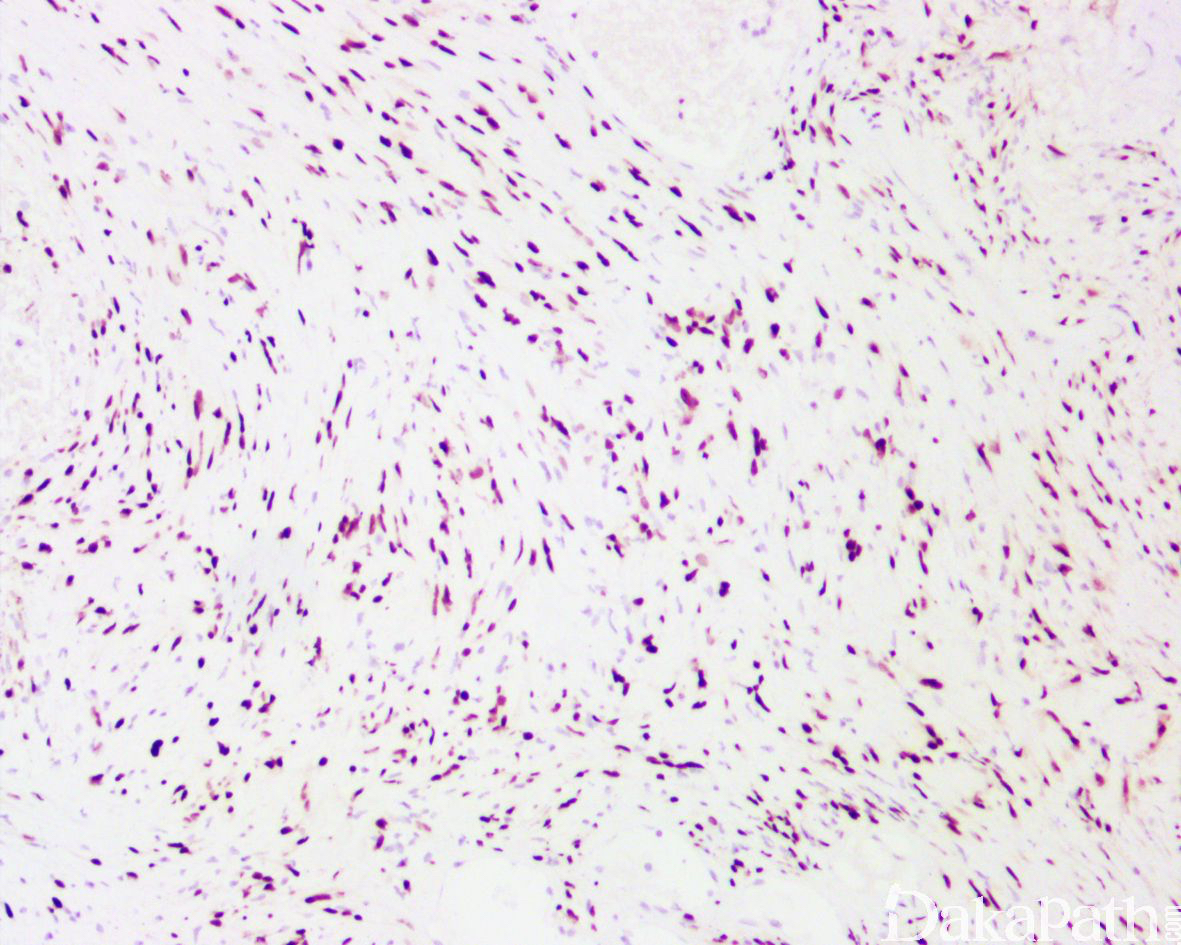

- 组织形态与发生于其它部位者相同,由梭形细胞构成,部分呈栅栏状排列(Antoni A),部分细胞少而结构疏松(Antoni B);

- 有些肿瘤呈富于细胞型神经鞘瘤改变,即富于细胞区完全或主要由 Antoni A 区构成,无 Verocay 小体。

免疫组织化学染色:

SOX10 和 S100 阳性,EMA、CK 阴性。